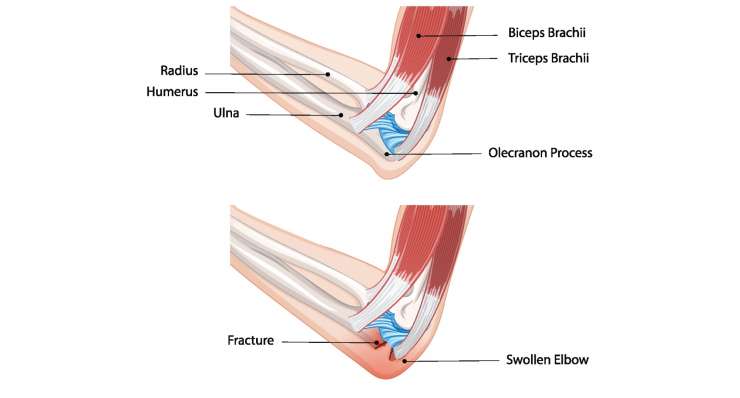

перелом локтя

В зависимости от типа травмы, профессор, доктор медицины Франк Мартечшлегер лечит перелом локтя консервативно или хирургически с помощью точных методов остеосинтеза, чтобы полностью восстановить стабильность и подвижность сустава.